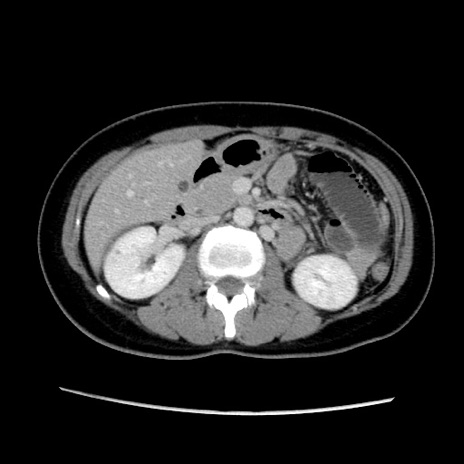

症例39(横断像)

【症例】40歳代女性

【主訴】上下腹部痛

【現病歴】2日目から下腹部痛あり。夜間は痛みで眠れなかった。昨日より上腹部痛と下痢が出現。臥位で痛みは軽快したため、休んでいた。本日になって臥位でも立位でも痛みが強くなってきたため救急要請。

【既往歴】子宮内膜症

【身体所見】部:平坦・軟、左上下腹部に圧痛あり、反跳痛あり。

【データ】WBC 21800、CRP 26.78